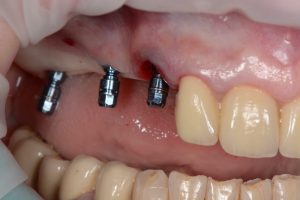

Os dois implantes adicionais na região do molar foram inseridos sem retalho após a perfuração da gengiva. Usando a guia cirúrgica, eles puderam ser inseridos bicorticalmente exatamente como planejado digitalmente, garantindo a utilização ideal do osso (Fig. 12 e Fig. 13) e alcançando uma alta estabilidade primária de 40 Ncm. O procedimento cirúrgico em si durou 30 minutos.

(Fonte: Dr. Jan Erik Jansohn)